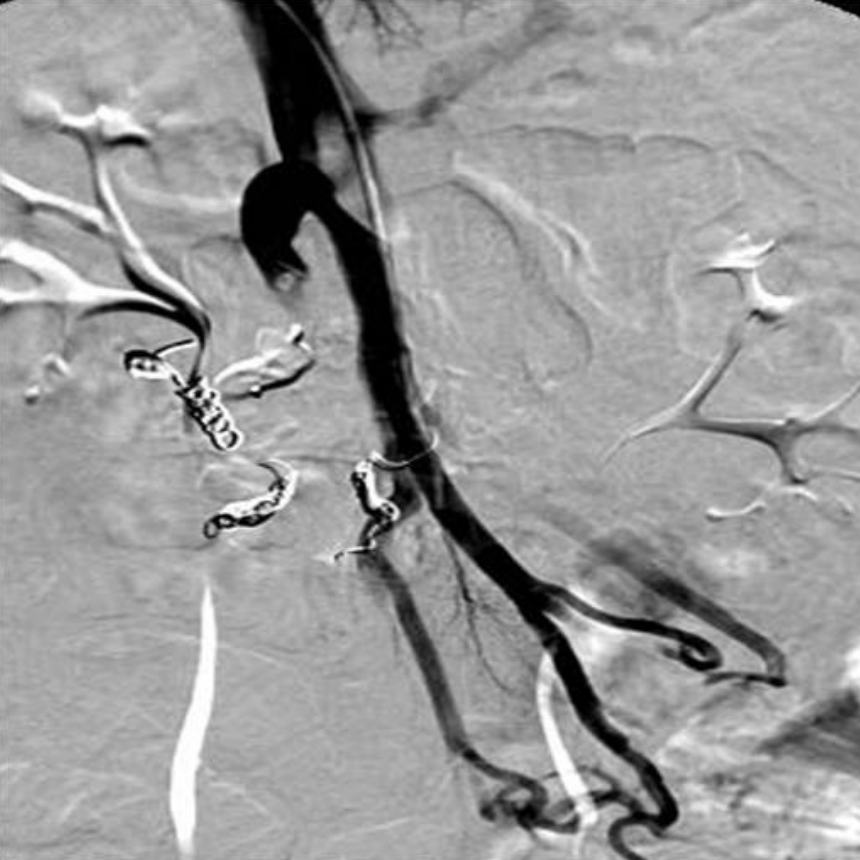

12mm AMPLATZER® Vascular Plug(AVP; AGA Medical, Golden Valley, MN)를 이용하여 주문맥의 원위부에서 기시하는 비후된 afferent vein에 대한 색전술을 시행함(Fig.3). 이후 시행한 direct portal venogram에서 상장간막 정맥으로부터 기시하여 varix nidus를 supply하는 3개의 측부혈관(collateral vessels)이 관찰되고 이로부터 varix의 nidus가 retrograde filling되는 소견이 지속적으로 관찰됨(Fig.4). 이에 대하여 2.4F microcatheter(Progreat®; Terumo, Tokyo, Japan)를 이용하여 각각의 측부혈관을 선택한 후 다수의 microcoils(Tornado®; Cook, Bloonminton, USA)을 이용하여 색전술을 시행함.

Fig. 3

The main trunk of jejunal varix is embolized with 12mm in diameter vascular plug (arrow).